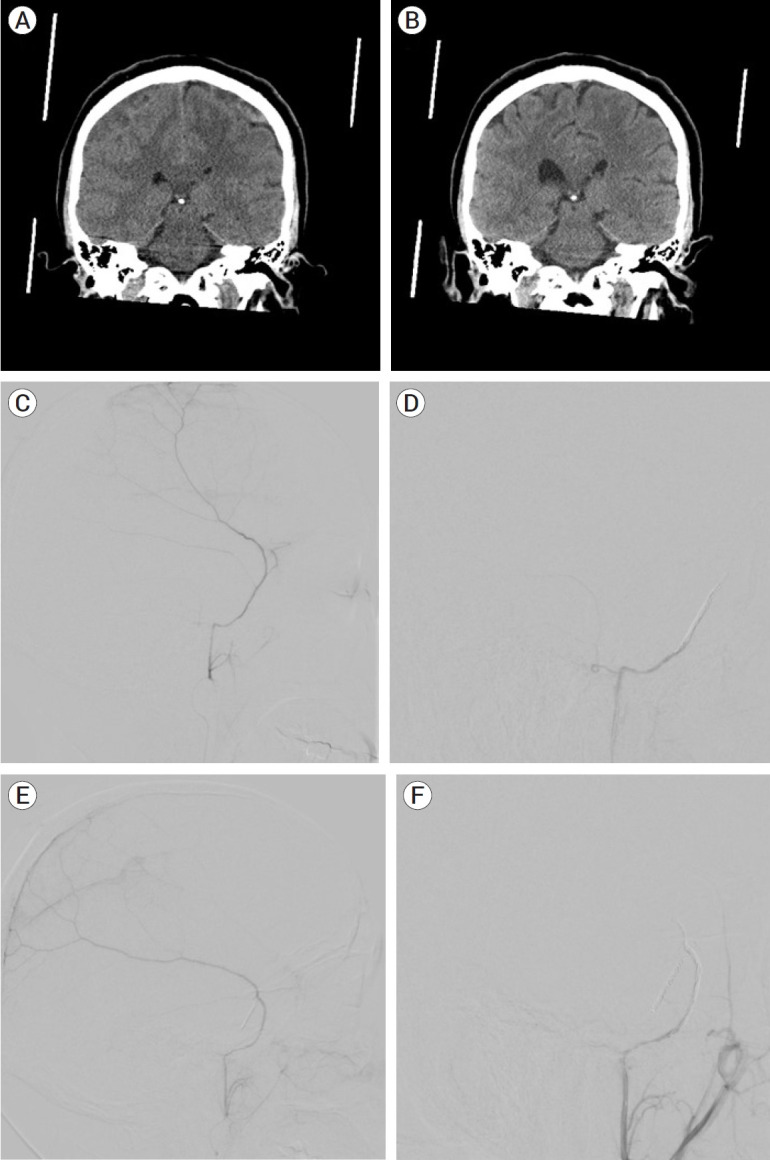

Methods: Four patients (3 females, 1 male, median age 77.5) with bilateral subdural hematomas were treated with bilateral MMA embolization. One hematoma of each patient was treated with coils and PVA, and the other was treated exclusively with coils. New or resolved symptoms, radiographic imaging demonstrating hematoma change, and complications were recorded and compared between the two treatment modalities. Minimum follow-up time was three months.

Results: All patients demonstrated symptomatic and radiographic improvement at three month follow-up. None of the patients in this cohort received surgical evacuation of the hematoma prior to or after embolization. One patient had previously been treated for hydrocephalus with a VP shunt. There were no postoperative complications. In the hematomas treated with a combination of coils and particles, three showed complete resolution with one showing interval improvement on imaging. All hematomas treated with coils alone demonstrated complete resolution after three months. Conclusions: Middle meningeal artery embolization with coils alone has demonstrated noninferior results to embolization with a combination of particle embolisate and coils in this small cohort.